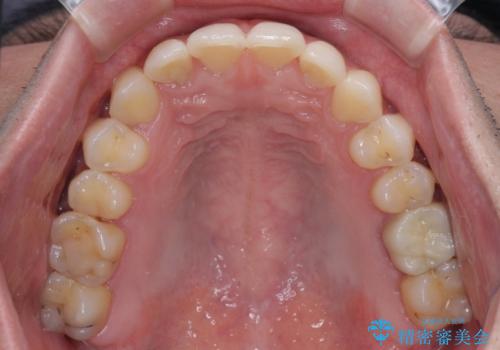

ディープバイトと叢生 インビザラインによる矯正治療

- 前歯のディープバイトと叢生を気にして来院された患者様です。

目立ちにくい装置を希望されていたため、ワイヤー装置とインビザラインを提案したところ、インビザラインを希望されました。

上下ともに叢生が認められたため、親知らずすべてを抜歯し、歯列全体を後方へ移動させることで歯列を整えることとしました。

上顎奥歯の銀歯も気になっていたので、矯正治療の途中でセラミッククラウンへ変更し、その後歯列を仕上げていくこととしました。

ディープバイトもデコボコも改善され、気になっていた銀歯もセラミックとなり、患者様には大変満足していただきました。